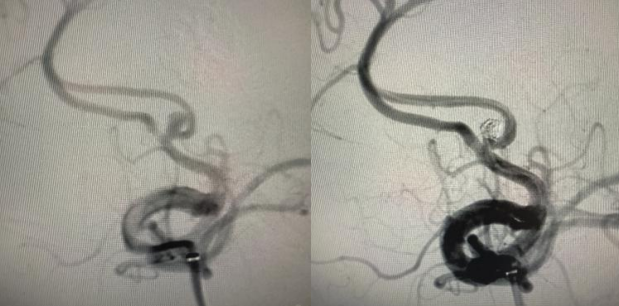

针对复发的前交通动脉瘤,小心将微导管送入瘤腔,缓慢填入栓塞材料,直至动脉瘤完全闭塞,同时确保载瘤动脉通畅,不影响正常脑组织供血;

针对新生动脉瘤,将载药支架精准送至目标位置并释放,术中多次通过血管造影确认支架贴壁良好、完全覆盖动脉瘤开口,在瘤颈处形成稳定的生物性封闭,实现血管重建。

整个手术历时约3小时,术中影像反复确认:两颗动脉瘤均完全闭塞,载瘤动脉及分支血流正常,无任何并发症迹象,手术圆满成功。